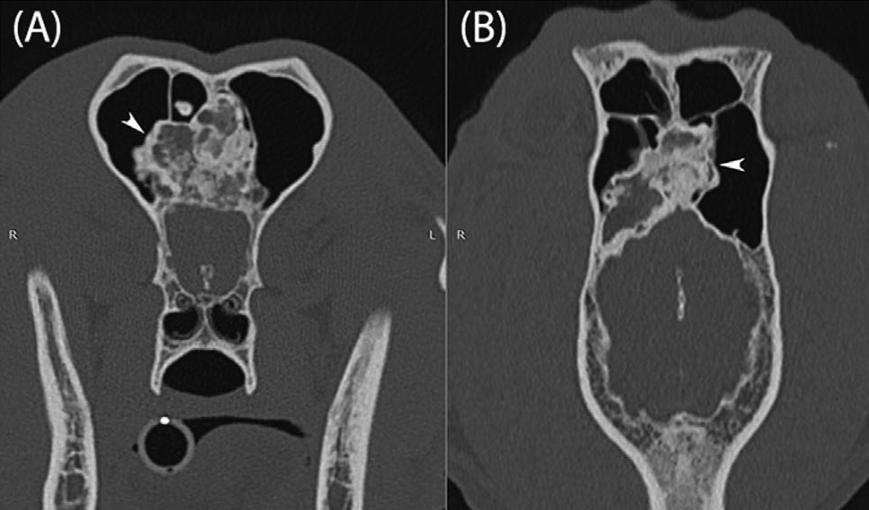

수술을 위해서는 뇌 내측으로 침습한 양상을 확인하기 위해 CT 촬영이 필요하다.

CT를 보고 침습범위 확인하고 수술 가능여부플 평가한 수 수술로 제거한 증례